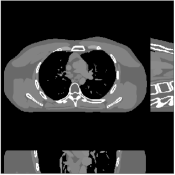

Recent works applied learned unions of transforms to other applications. For example, the union of transforms model was pre-learned (from a dataset) and used in a clustering-based low-dose 3D CT reconstruction scheme [26]. Fig. 4 shows an example of high quality reconstructions obtained with this scheme. While the work used a PWLS-type reconstruction cost, a more recent method [132] replaced the weighted least squares data-fidelity term with the shifted-Poisson likelihood penalty, which further improved image quality and reduced bias in the reconstruction in ultra low-dose settings. Other recent works combined learned union of transforms models with material image models and applied it to image-domain material decomposition in dual-energy CT with high quality results [137, 138].